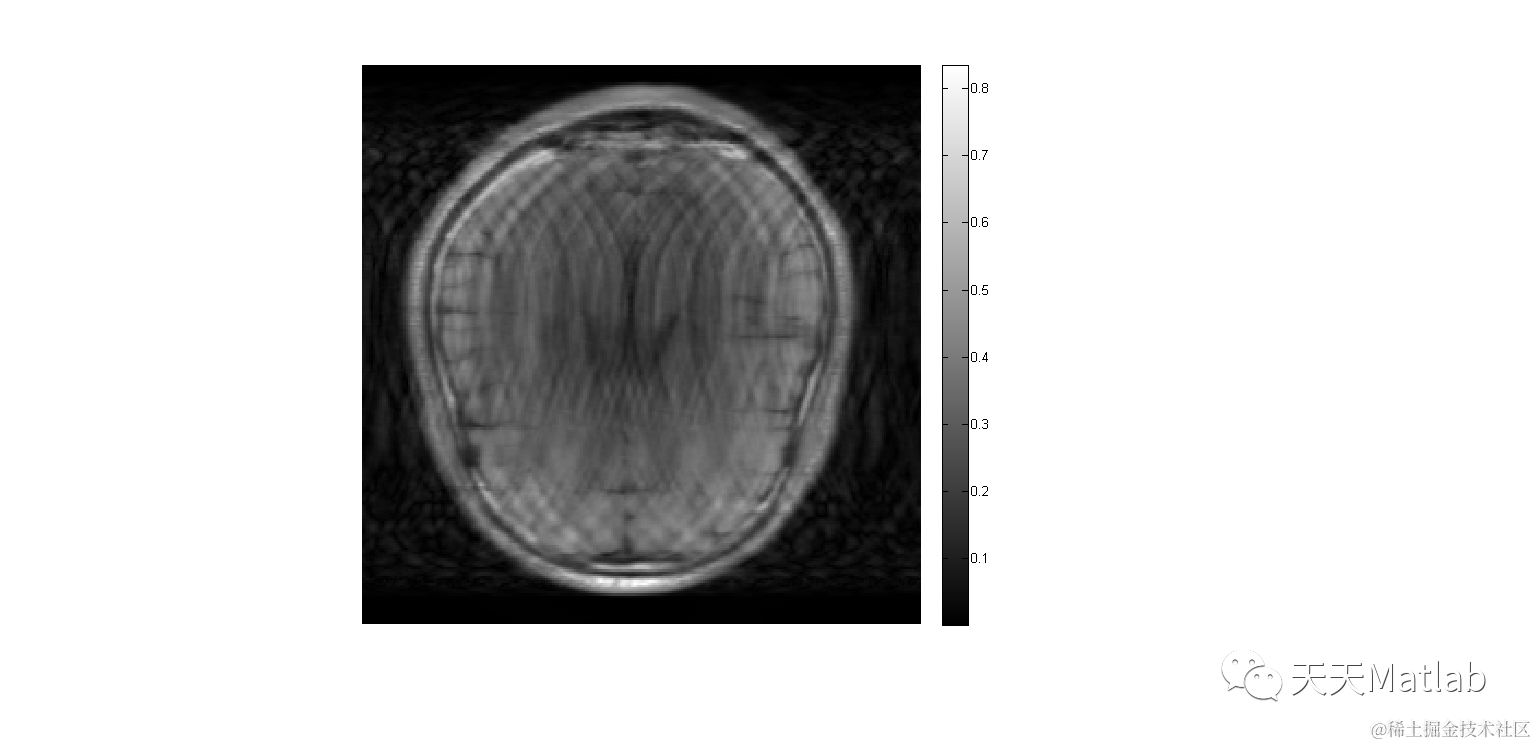

小波 分析

» 小波 分析 代码 (93) 사진

小波 分析 代码 (93) 사진